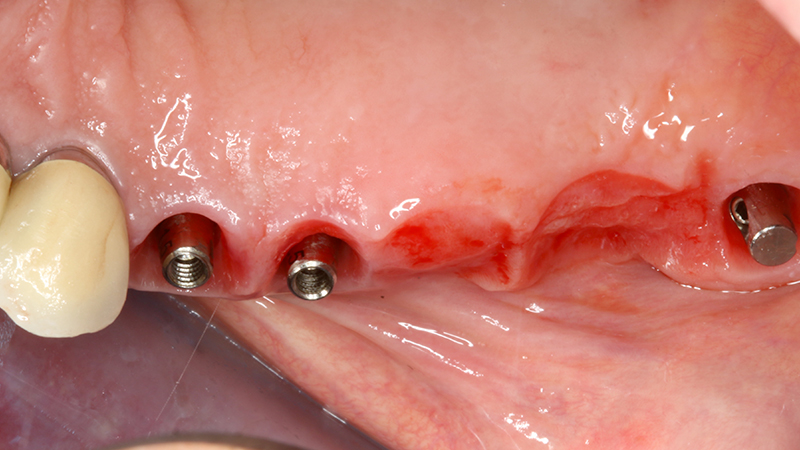

Sul 12 veniva eseguito un impianto post-estrattivo con carico immediato mediante moncone conometrico e provvisorio ricavato ribasando una cappetta provvisoria in peek e applicazione a frizione mediante conometria (Figs. 19, 20, 21, 22, 23).

Carico immediato su 12 con moncone conometrico dritto e cappetta provvisoria in peek ribasata in resina su provvisorio. Foto dopo l'intervento con esecuzione flapless e leggera plastica gengivale del Tuber applicazione di cappette di guarigione in peek. Guarigione dei tessuti dopo 3 mesi e impronta digitale definitiva per finalizzare il caso

Fig. 19, 20 - Carico immediato su 12 con moncone conometrico dritto e cappetta provvisoria in peek ribasata in resina su provvisorio. Foto dopo l'intervento con esecuzione flapless e leggera plastica gengivale del Tuber applicazione di cappette di guarigione in peek. Guarigione dei tessuti dopo 3 mesi e impronta digitale definitiva per finalizzare il caso